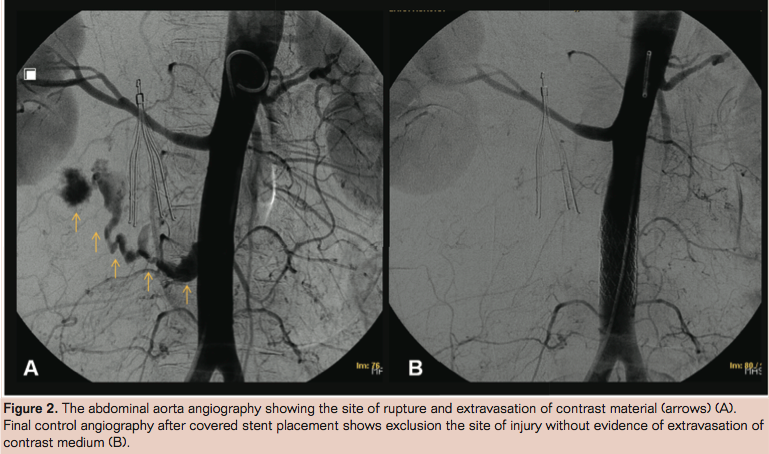

Five days after the procedure, she was admitted to the emergency department with abdominal pain and hemodynamic instability. A multislice computed tomography (MSCT) scan showed active bleeding in the back of the infrarenal abdominal aorta (Figure 1). A substraction angiography confirmed the findings of the MSCT (Figure 2A), and then endovascular treatment was performed by placing a 16 x 41mm Advanta V12 Atrium balloon-expandable covered stent (Atrium Medical Corporation), which closed the site of bleeding (Figure 2B).